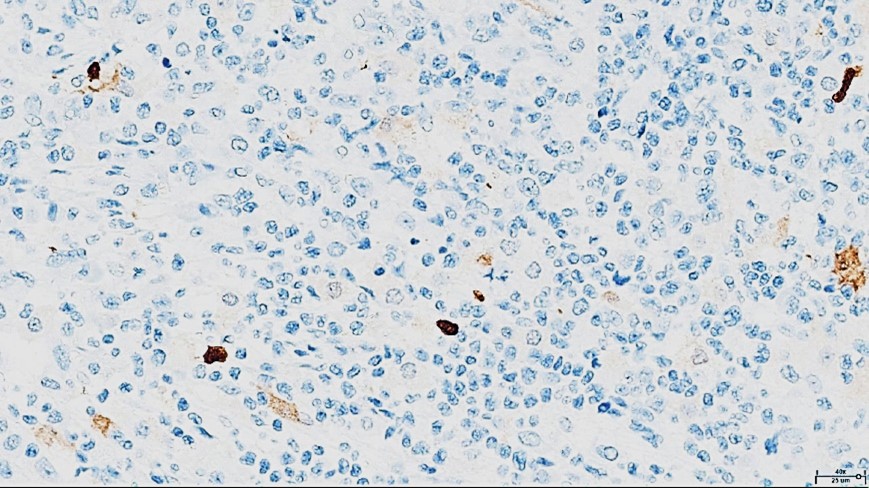

Histopathological examination revealed a non-circumscribed proliferation of large cells with marked nuclear pleomorphism, prominent nucleoli, and abundant clear cytoplasm, with numerous mitotic figures (Figure 3). Immunohistochemistry showed strong and diffuse expression of CD30 in atypical cells (Figure 4), and positivity for granzyme B, CD2, CD4, and CD25 in atypical T-cells (Figure 5). Numerous intermingled histiocytes were positive for CD68 and CD163, but negative in the atypical cells (Figures 6 and 7). ALK1 was negative in lymphoid cells (Figure 8). These findings supported the diagnosis of primary cutaneous anaplastic large cell lymphoma. Laboratory and PET-CT evaluation showed no extracutaneous disease. Localized electron beam radiotherapy was performed.

Figure 8: Immunohistochemistry for ALK1 (40x): Negative in atypical lymphoid cells.